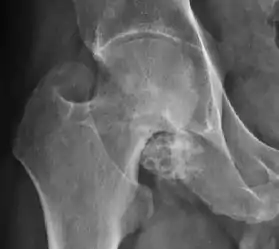

Plain radiography allows us to categorize the hip as normal or dysplastic or with impingement signs (pincer, cam, or a combination of both). Besides these, pathologic processes like osteoarthritis, inflammatory diseases, infection, or tumors can also be identified (Figure 1).[1]

Figure 1.

Hip in osteoarthritis

- Osteoarthritis

In adults, one of the main indications for radiographs is the detection of osteoarthritic changes (Figure 1(e)). Nevertheless, radiographs usually detect advanced osteoarthritis that can be graded according to the Tönnis classifications. The grading system ranges from 0 to 3, where 0 shows no sign of osteoarthritis. Intermediate grade 1 shows mild sclerosis of the head and acetabulum, slight joint space narrowing, and marginal osteophyte lipping. Grade 2 presents with small cysts in the femoral head or acetabulum, moderate joint space narrowing, and moderate loss of sphericity of the femoral head. Grade 3 is the severest form of osteoarthritis, which manifests as severe narrowing of the joint space, large subchondral cyst with productive bone changes that may lead to deformity of the bone components of the joint, while secondary osteoarthritis due to calcium pyrophosphate deposition can be diagnosed when calcification of hyaline cartilage and fibrocartilage is detected.[1]

Synovial chondromatosis can be confidently diagnosed by X-ray when calcified cartilaginous chondromas are seen. However, other synovial proliferative processes, such as pigmented villonodular synovitis, require MRI for accurate diagnosis, although noncalcified synovitis can be suspected in radiographs by indirect signs, such as soft tissue swelling and/or erosions in the femoral head, femoral neck, or acetabulum (Figure 7).[1]

X-ray of synovial chondromatosis.[1]